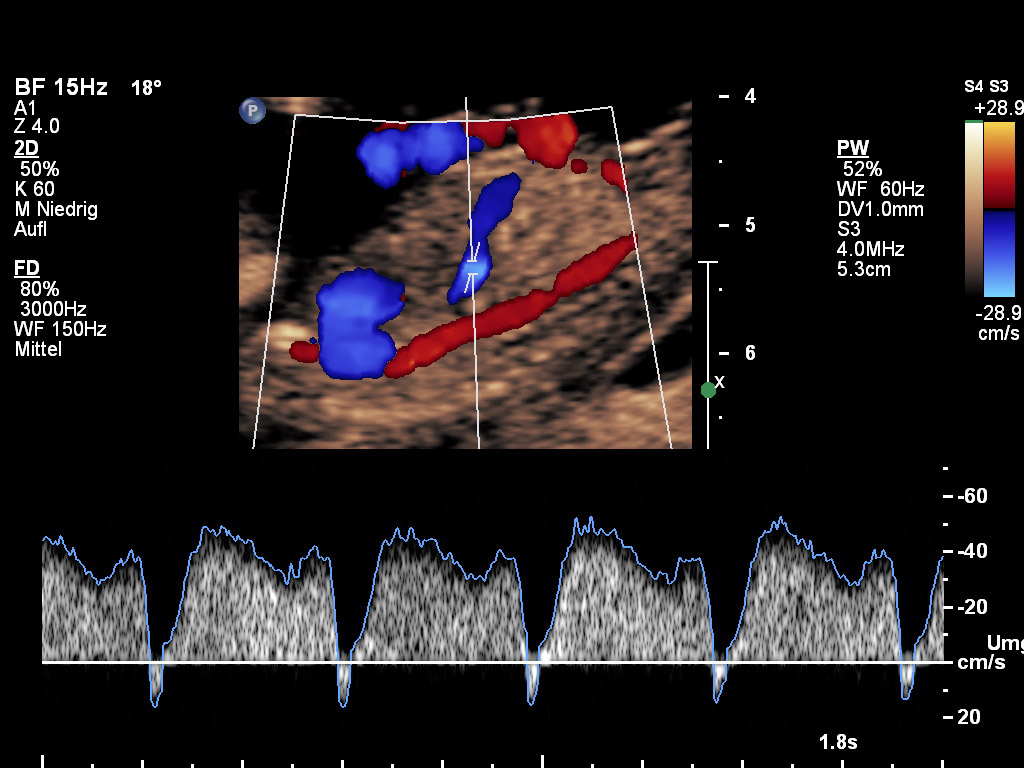

1. den Blutfluss durch die rechte große Klappe im rechten fetalen Herzen messen und auf einen möglichen Rückfluss überprüfen (Trikuspidalregurgitation).

2. den Zufluss zum fetalen Herzen messen (Ductus-venosus-Fluss). Sollte sich das Blut vor dem Herzen stauen, sind Herzfehler und Störungen in den Erbanlagen häufiger.